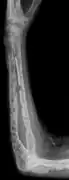

X-ray of the forearm, with lytic lesions

Multiple myeloma in the upper arm

Humerus with multiple myeloma lesions

Same humerus before, with just subtle lesions

The diagnostic examination of a person with suspected multiple myeloma typically includes a skeletal survey. This is a series of X-rays of the skull, axial skeleton, and proximal long bones. Myeloma activity sometimes appears as "lytic lesions" (with local disappearance of normal bone due to resorption) or as "punched-out lesions" on the skull X-ray ("raindrop skull"). Lesions may also be sclerotic, which is seen as radiodense.[70] Overall, the radiodensity of myeloma is between −30 and 120 Hounsfield units (HU).[71] Magnetic resonance imaging is more sensitive than simple X-rays in the detection of lytic lesions, and may supersede a skeletal survey, especially when vertebral disease is suspected. Occasionally, a CT scan is performed to measure the size of soft-tissue plasmacytomas. Nuclear Medicine Bone scans are typically not of any additional value in the workup of people with myeloma (no new bone formation; lytic lesions not well visualized on nuclear bone scan).